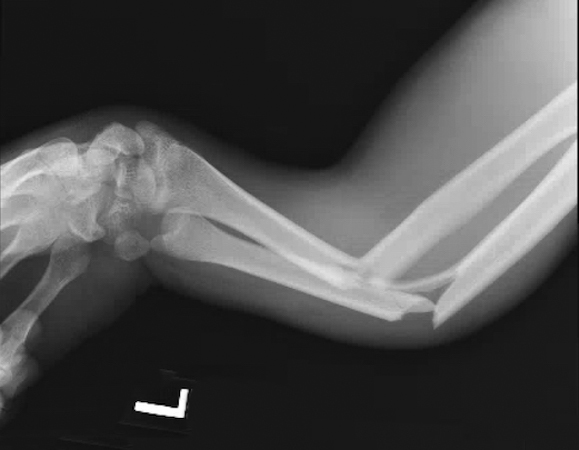

Monteggia fracture

- A Monteggia fracture involves a fracture of the proximal third of the ulna combined with a subluxation or dislocation of the radial head at the proximal radioulnar joint (PRUJ) and the humeroradial joint.1,11,12

- These injuries most commonly occur secondary to a direct blow to the posterior aspect of the ulna, with the elbow extended and the forearm in hyperpronation.16,17

- Monteggia fractures account for <2% of all forearm fractures and are more common in pediatric patients than adults. In children and adolescents, they are usually caused by sports injuries, falls from a height, or motor vehicle accidents.11,13,16

Imaging17

- Radiology studies - X-ray

- AP and lateral orthogonal views with an oblique view are usually adequate.3